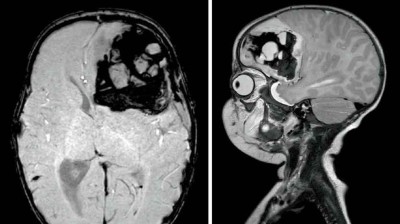

Was blockiert die Atemwege dieser Neugeborenen?

Gerade erst geboren, fallen bei dem sonst gesunden, reifen Mädchen Atemprobleme auf. Schuld ist eine Raumforderung an der Racheninnenwand. Eine MRT des Halses zeigt eine 3 × 3 × 1,5 cm große Läsion im Bereich des Nasopharynx. Wie würden Sie hier weiter vorgehen und die Atemwege sichern?